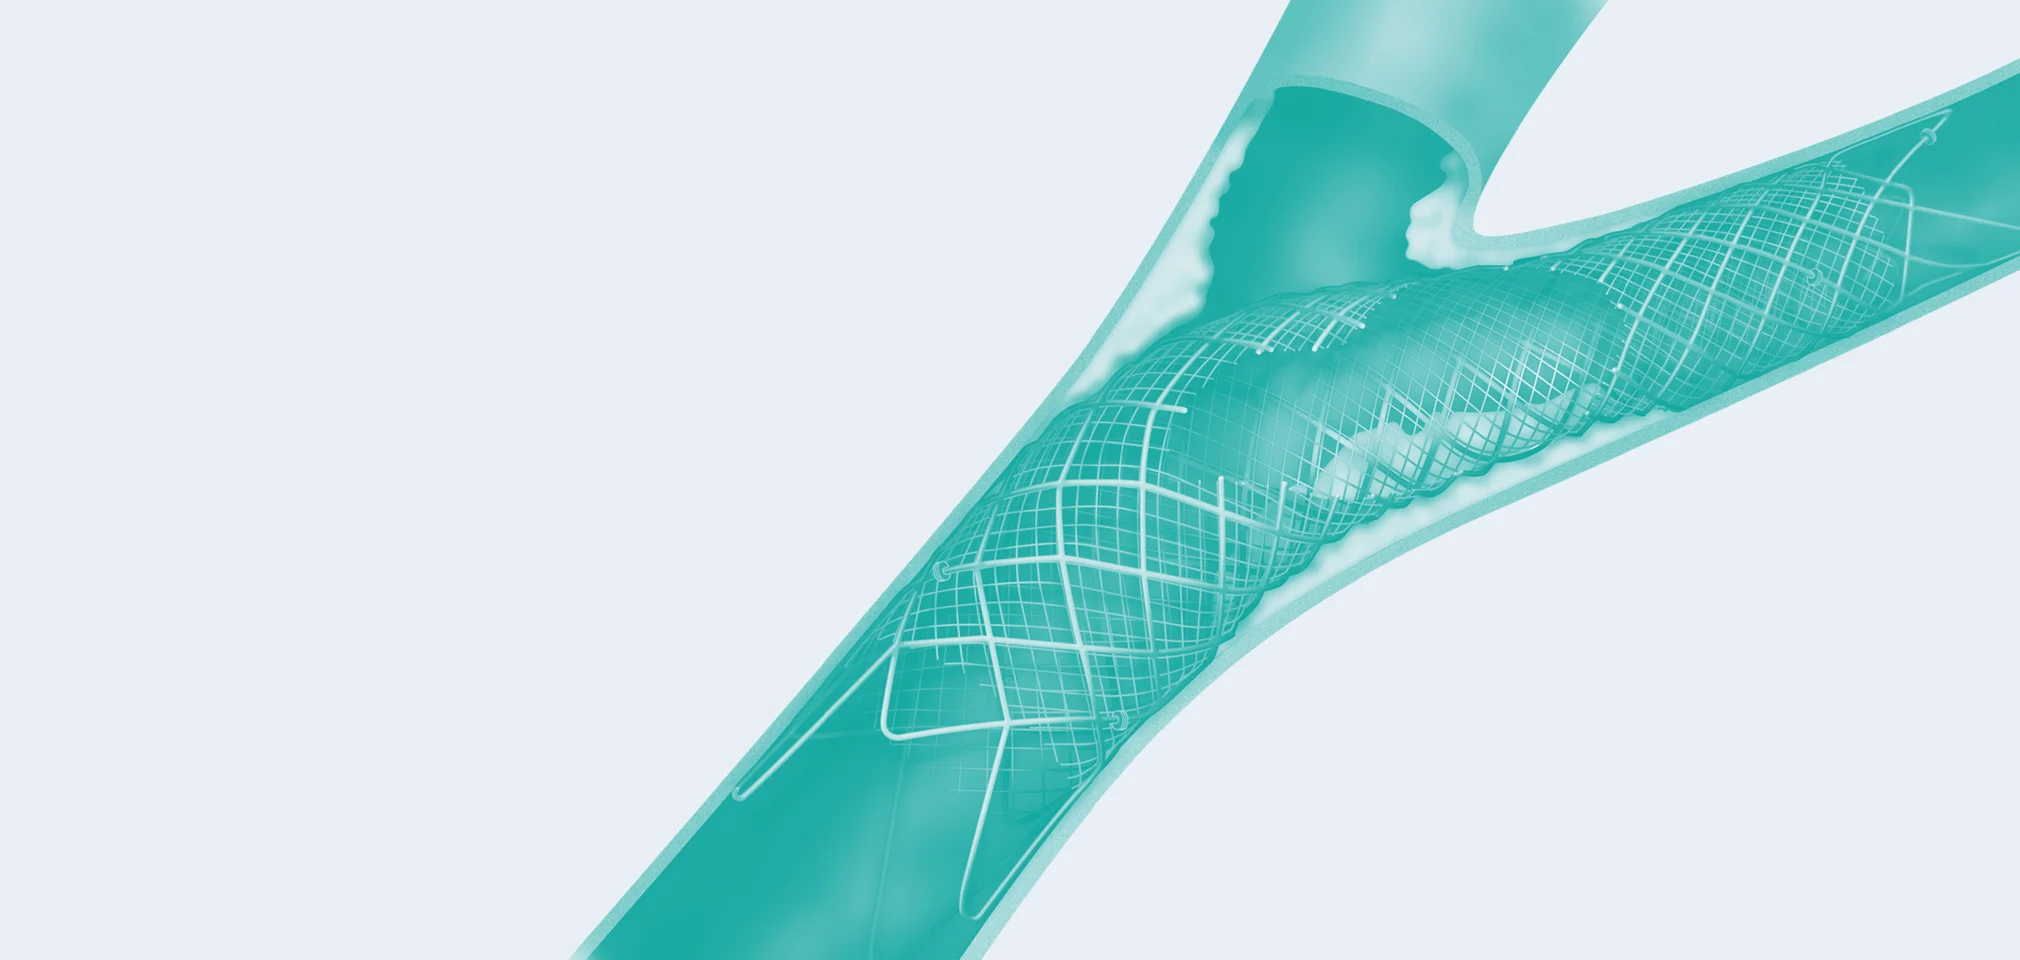

02 — Carotid Stenting

Carotid artery stenting (CAS) is an endovascular procedure where a stent is deployed within the lumen of the carotid artery to treat narrowing of the carotid artery and decrease the risk of stroke.